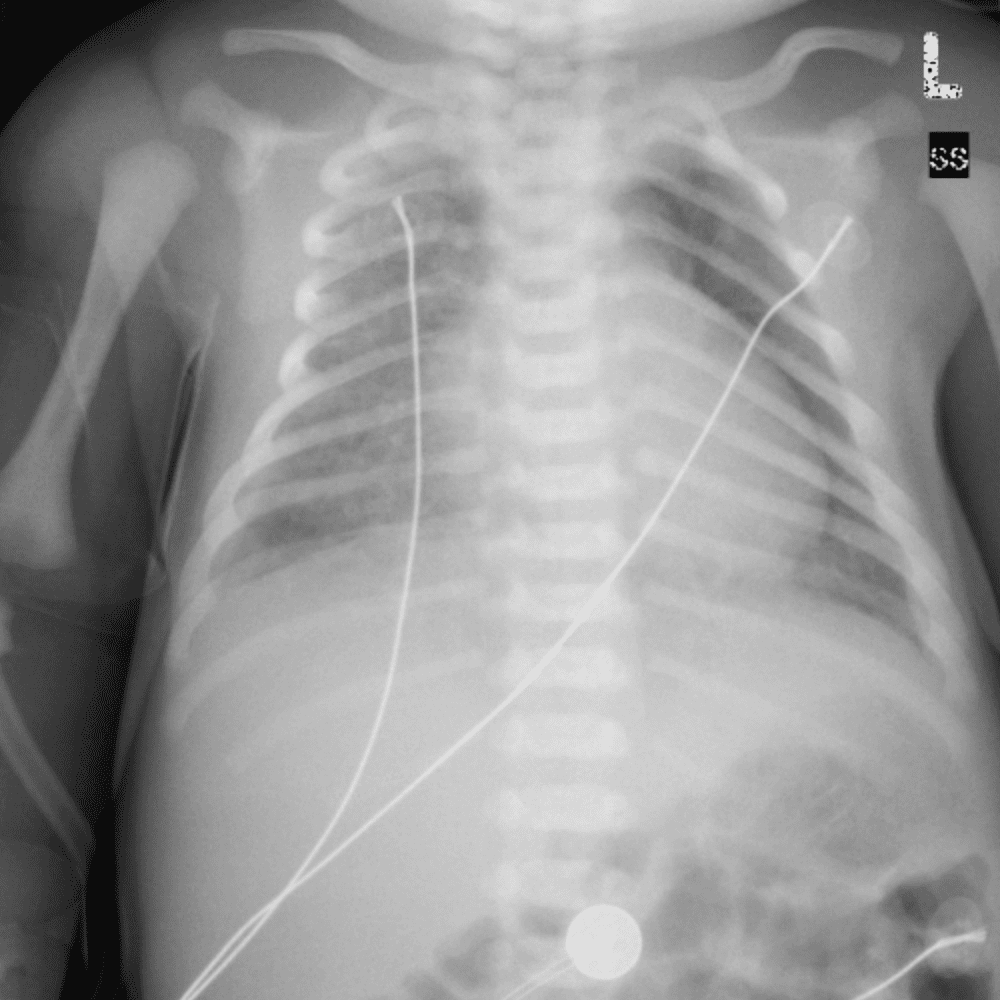

Peds Chest

Practice

Simulates call by including subtle or difficult cases and some normals.

50 cases